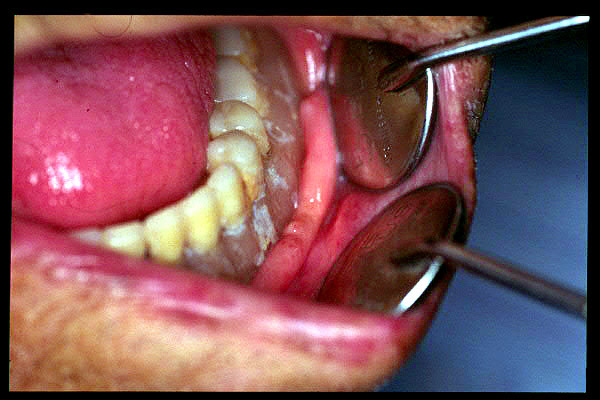

CM Enfermedad periodontal avanzada